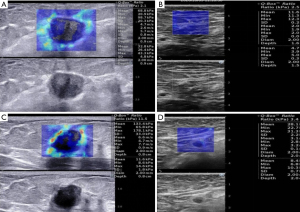

For SWE evaluation, the scale of the elastic color image is set to 0–180 kPa. Lesion and accompanying normal tissues are identified as the system region of interest (ROI). The initial fixed Q-Box of 2×2 mm2 was put in the toughest section of the lesion, along with the nearby hard tissue or halo. A second Q-Box with the same scale was positioned outside the lesion in healthy adipose tissue as a comparison. Maximum stiffness (Emax, kPa), mean stiffness (Emean, kPa), stiffness ratio (Eratio), and stiffness standard deviation (Esd, kPa) was reported.

Univariate analysis of SWE parameters between the limited nodal burden group and the high nodal burden group as revealed in Table 3. There are significant variations between the two groups in the median SWE values of Emax (P=0.001), Emean (P=0.002), Esd (P=0.001) derived from tumors. The median SWE values in ALN between the two groups in Emax (P<0.001), Emean (P<0.001), Eratio (P<0.001), Esd (P<0.001) is statistically important. All SWE parameters of the high nodal burden group were larger than those of the limited nodal burden group.

We further evaluated the diagnostic efficiency of SWE for the prediction of high nodal burden group with the optimal cutoff values. The SWE values in the limited nodal burden group and the high nodal burden group were shown in Figure 2. The optimum cutoff value was as follows: 119.52 kPa for tumor Emax, 97.31 kPa for tumor Emean, 19.38 for tumor Esd, 26.22 kPa for ALN Emax, 19.79 kPa for ALN Emean 2.32 for Eratio of ALN, 3.34 for Esd of ALN. The area under the curve (AUC), Sensitivity (Sen), Specificity (Spe), Diagnostic Accuracy (ACC), Positive Predictive Value (PPV), Negative Predictive Value (NPV) with optimum cutoff values are shown in Table 5. In conjunction with sensitivity and specificity scores, Emax of ALN could be chosen as the ideal index if maximum diagnostic performance was considered (AUC: 0.856; 95% CI: 0.802–0.909). The ROC curve is demonstrated in Figure 3.

Without first discovering by ultrasound, those unusual lymph nodes present do not stand to gain from fine needle aspiration or core needle biopsy. SWE contains details on the stiffness of the tissue examined based on traditional ultrasound, which gives it a great benefit in the area of breast cancer detection. This research focuses on the overall evaluation of the existence of a high nodal burden by SWE observations of primary breast cancer, except those who do not require ALND, and presents a significant alert to sonographers prior to axillary exams. The burden status was again determined by the assessment of the elastography of the lymph node. We explored the use of SWE for tumor and ALN assessment and discovered that all elasticity indices in the high nodal burden group were substantially higher than the limited nodal burden group, except for the tumor Eratio value. The median Emax and Emean in tumor, and the median Esd in ALN were independently associated with high nodal burden. Evans et al. (12) recorded that the median Emean of IBC had 3 nodal statuses: 105 kPa for the node-negative group, 130 kPa for the 1–3 node-positive group, and 149 kPa for the 4 or more node-positive group, but did not present the optimal cutoff values. Since the subsets of the sample are different, my median findings for Emean are smaller than for the research (106.7 kPa for the limited nodal burden group, 123.9 kPa for high nodal burden group). This disparity may be due to patient inclusion requirements. Furthermore, the findings are influenced by the probe and setting of the ultrasonic instrument and by the operator’s manipulation.

We perceived that Emax of ALN has dependable application value in the diagnosis of lymph node burden in IBC. Detective performance of SWE characteristics of metastatic ALN in another study (27) was similar to ours, with the highest cutoff value being 25.8 kPa for Emax, 18.7 kPa for Emean, 2.7 for Eratio, 4.0 for Esd. To put it another way, if they were tested for high nodal burden, their findings could be higher than ours. This is due to data bias since our research was confined to clinical T1-T2N0 patients and was not used in patients with clinical palpation positive ALN, the ALN is lower in scale than other patients. The magnitude of the lesion is known to influence the elastic value calculated by SWE, and the elastic value of the bigger lesions is higher (28-30).